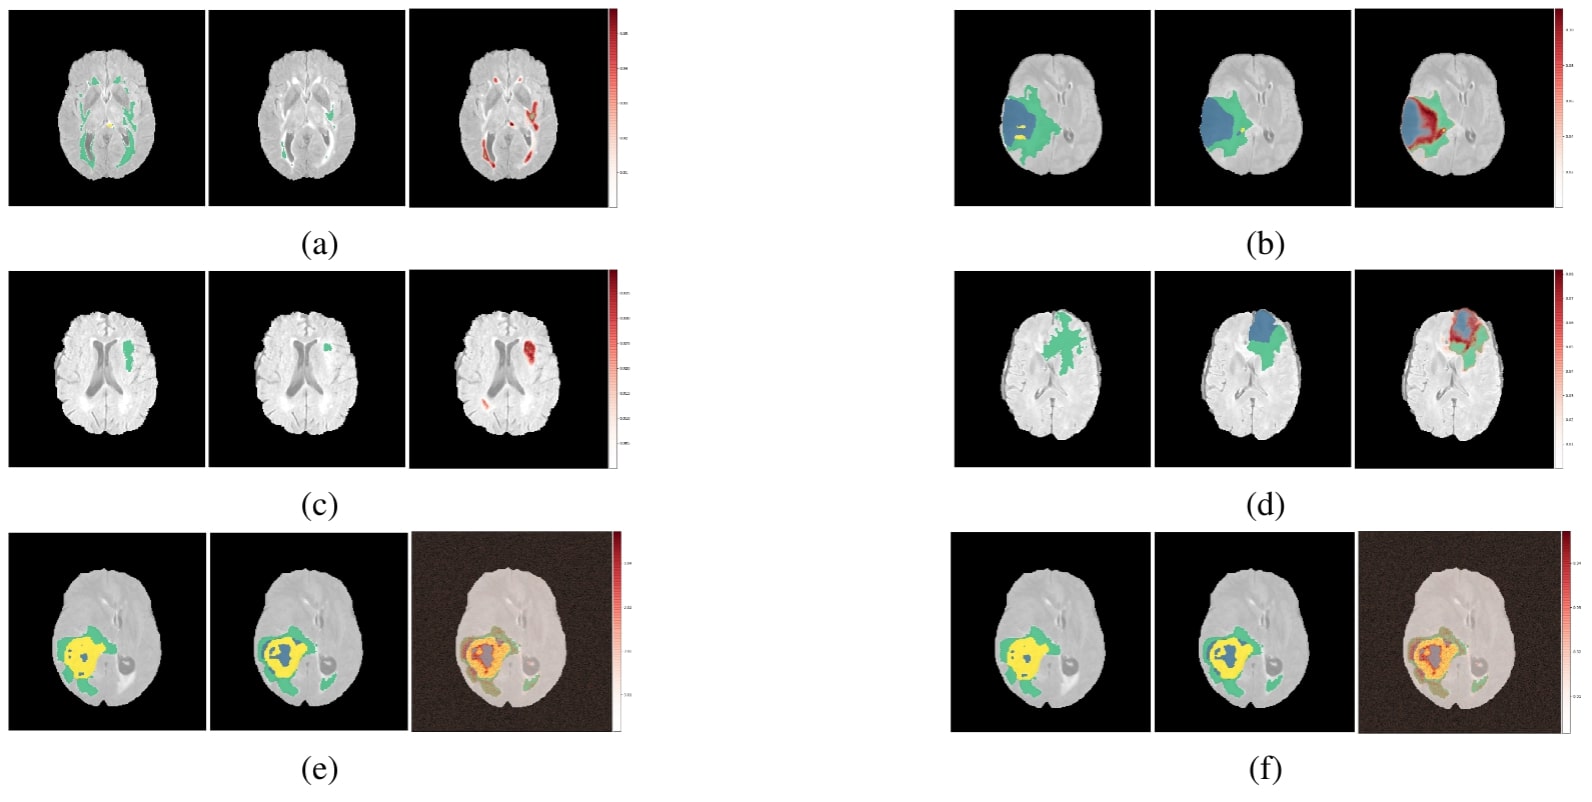

The results of this experiment, shown in Figures 2, 3, and 4, indicate that individual filters of brain-tumor segmentation networks learn explicit as well as implicit disentangled concepts. For example, Figure 2(e) shows a filter learning the concept whole tumor region i.e. it specifically detects the whole tumor region for any image in the input distribution, the filter in 2(b) seems to be learning the edema region, while 2(a) shows a filter learning the white and grey matter region, an implicit concept which the network is not trained to learn. Similar behaviour is seen in all networks (Figures 2, 3, 4).This means that we can make attributions based on function to the network at a filter level - indicating a sort of functional specificity in the network i.e. individual filters might be specialized to learn separate concepts.

Refer to caption

Figure 2: Disentangled concept mask M𝑀M learned by individual filters of the ResUnet overlaid over brain image. This includes explicit concepts for which ground truth labels are available as well as implicit concepts for which their are no labels. IoU scores are mentioned in the sub-captions for all 3 images.(L:Layer, WT: Whole Tumor, TC: Tumor Core, ED: Edema)

Figure 3: Disentangled concepts learned by filters of the DenseUnet. (L:Layer, WT: Whole Tumor, TC: Tumor Core, ED: Edema)

Figure 4: Disentangled concepts learned by filters of the SimUnet. (L:Layer, WT: Whole Tumor, TC: Tumor Core, ED: Edema)